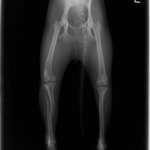

症例3:キルシュナーワイヤーのピンニングによる整復

ペルシャ猫 11ヶ月齢 雄

他院にて左大腿骨遠位の成長板骨折(salter-harrisⅠ型)が認められており、治療相談を目的として来院。当院にて、キルシュナーワイヤーを用いたピンニングにより骨折部位の整復を行いました。術後の経過は良好で、現在も経過観察中です。

術前レントゲン

術後レントゲン